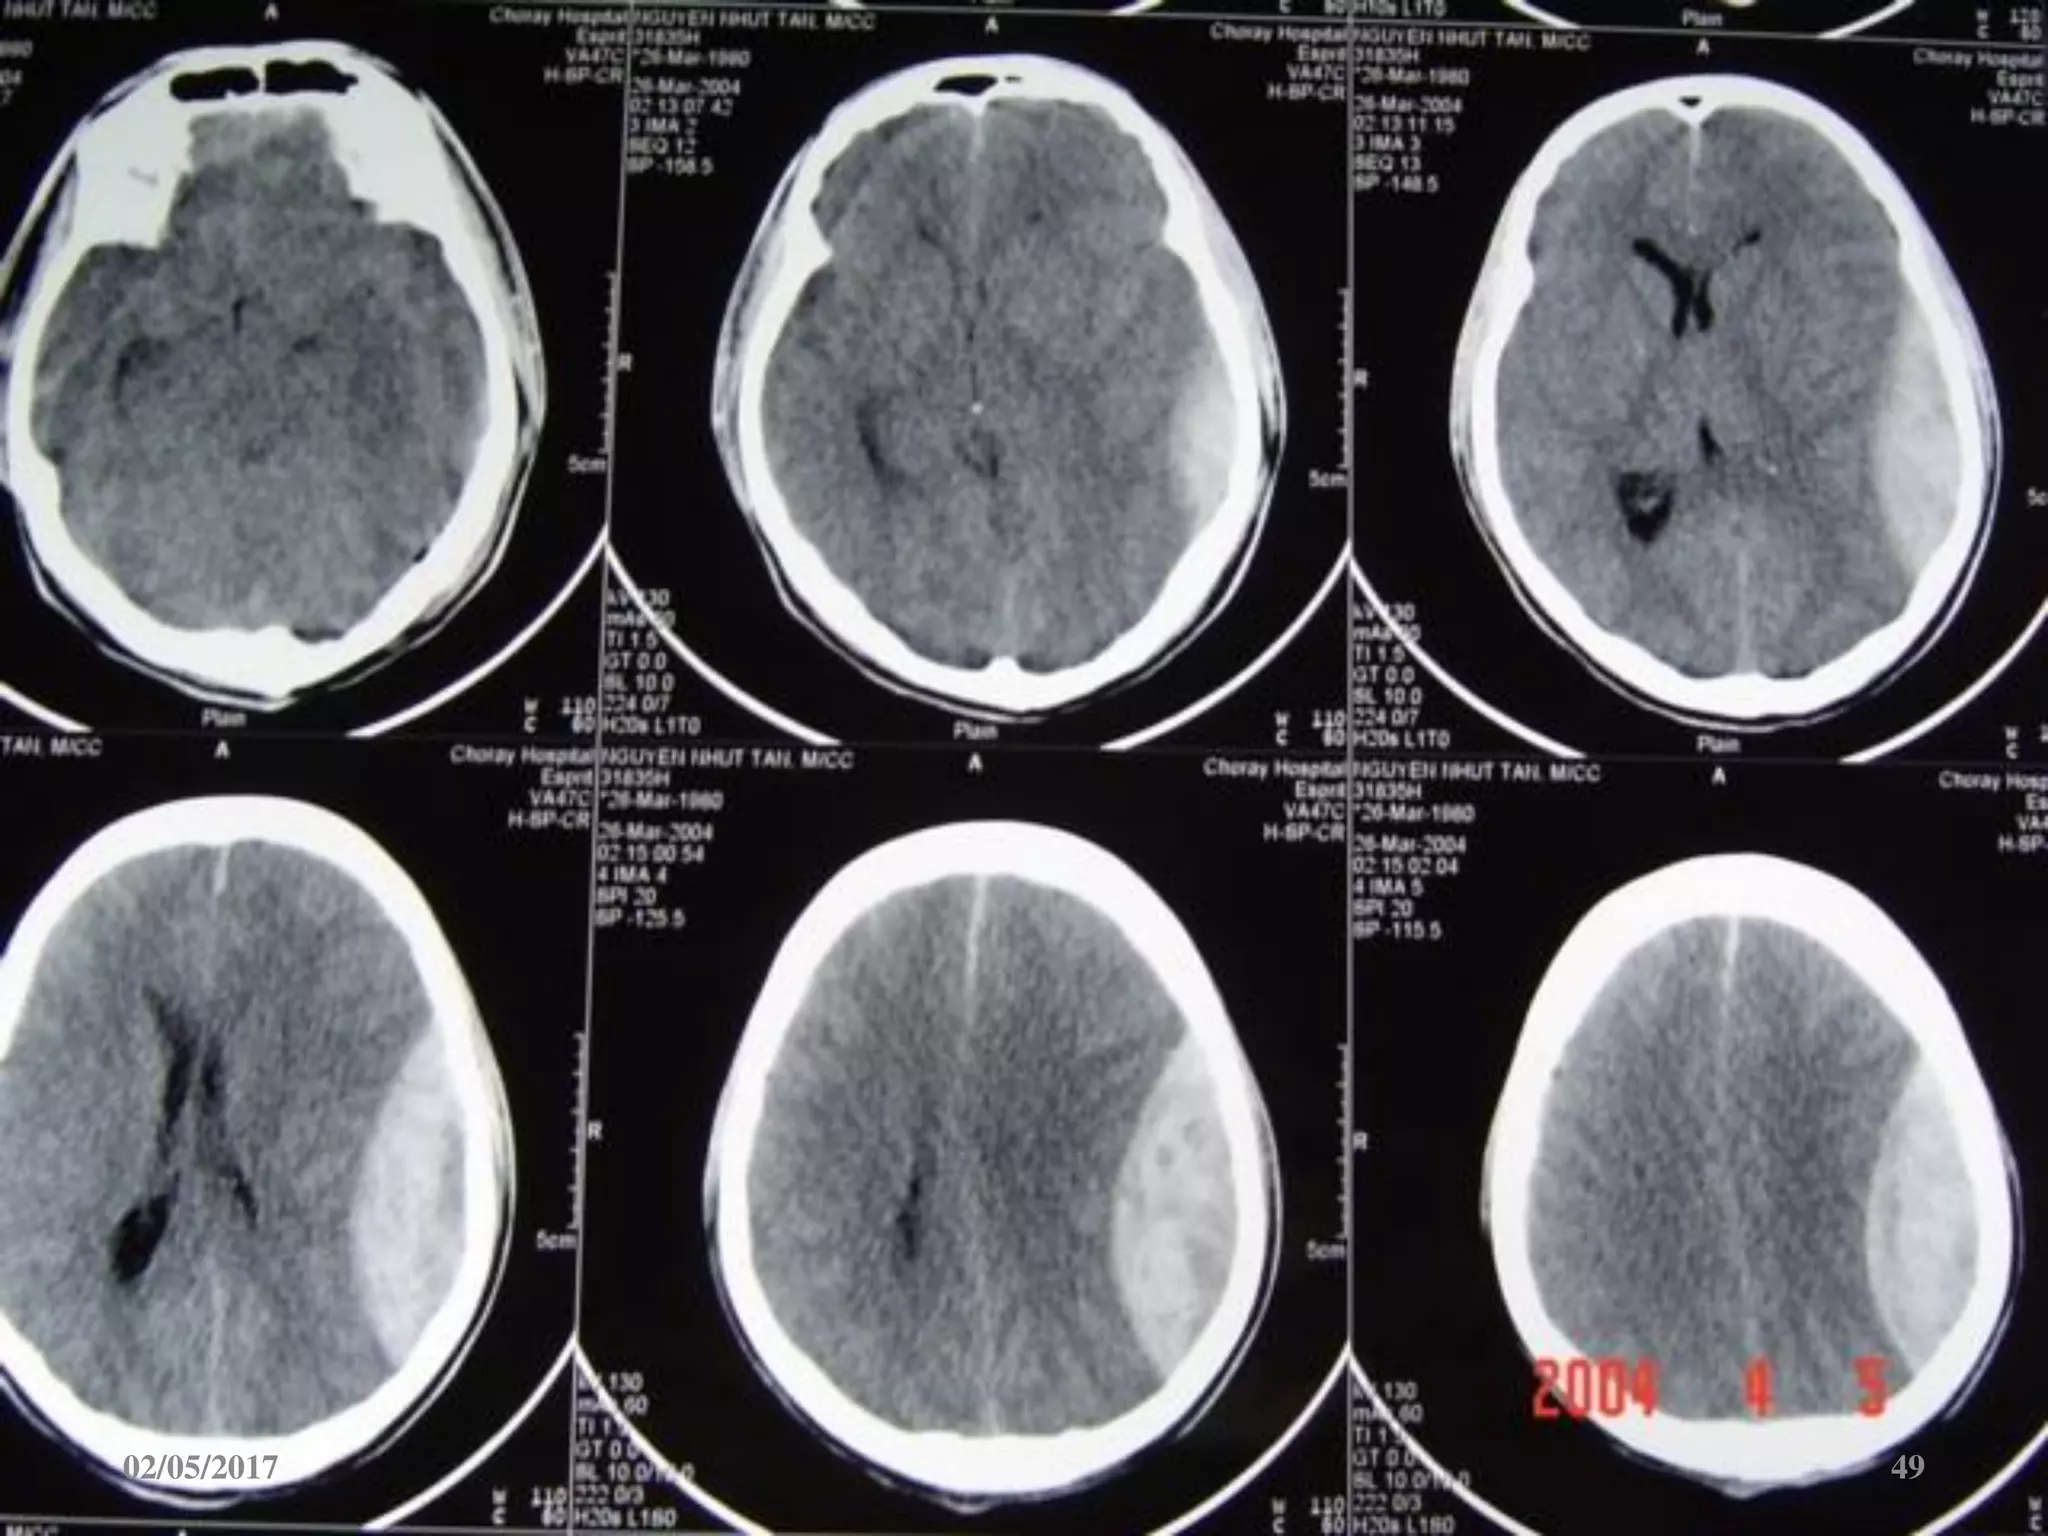

Phù não

• Giảm đậm độ lan tỏa.

• Mất ranh giới chất

trắng-xám.

• Xóa các rãnh não-bể

não.

• Não thất 2 bên nhỏ.

02/05/2017 67

02/05/2017 68